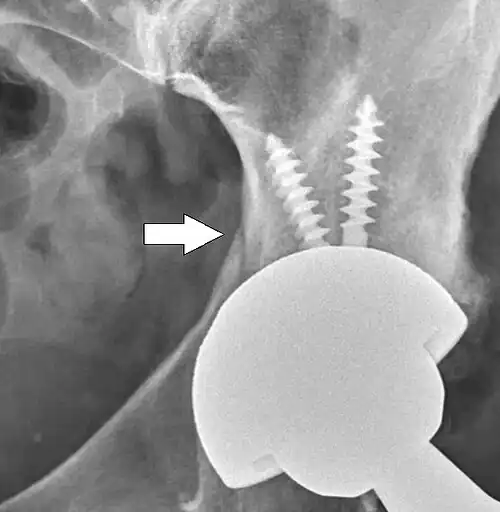

Dislocated artificial hip

Liner wear, particularly when over 2 mm, increases the risk of dislocation.[15] Liner creep, on the other hand, is normal remoulding.[16]

Dislocation (the ball coming out of the socket) is one of the most common complications. Hip prosthesis dislocation mostly occurs in the first three months after insertion, mainly because of incomplete scar formation and relaxed soft tissues.[15] The chance of this is diminished if less tissue is cut, if the cut tissue is repaired and if large diameter head balls are used.[17] Surgeons who perform more operations tend to have fewer dislocations. Important factors which are related to dislocation are: component positioning, preservation of the gluteal muscles and restoration of leg length and femoral offset.[18] Keeping the leg out of certain positions during the first few months after surgery further reduces risk.